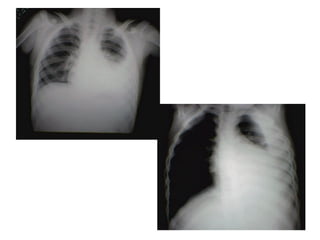

 Derrame pleural

 Pneumatoceles

 Pneumotórax /piopneumotórax

 Pneumonia necrotizante/Abscesso pulmonar

outras.

Complicações

1 2